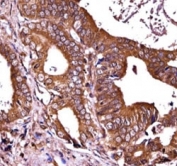

RIPK1 antibody immunohistochemistry analysis in formalin fixed and paraffin embedded human prostate carcinoma.

IHC (Paraffin) : 1:10-1:50